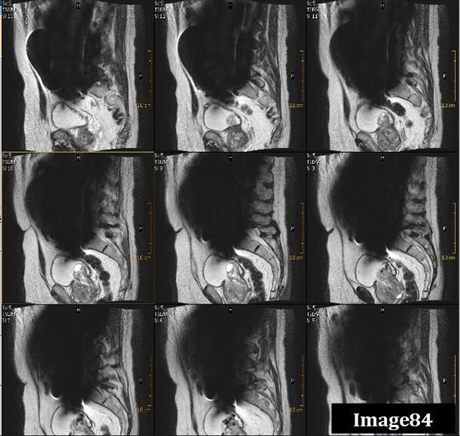

Image 84 displays what type of artifact

Magnetic susceptibility